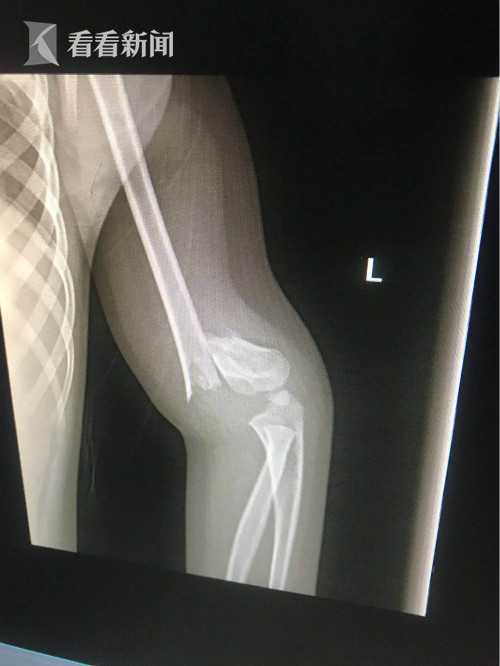

兵兵的叔叔王先生在电话中告诉看看新闻Knews,兵兵当场受伤严重,胳膊看着摔成了三截。对方肇事孩子的家长见此情况,立刻抱起自家孩子就离开了现场。由于只有兵兵妈妈带着他外出,所以她只顾着关心孩子伤情,无暇再去追肇事孩子及其家长。

受伤严重的兵兵转院到洛阳治疗,经检查左肱骨髁上完全骨折,由于淤血严重,暂时还无法进行手术。兵兵的叔叔称,最快可能明日(7月10日)进行手术,但术后极有可能留下后遗症。目前,受害者家人已报警,但肇事孩子及家长尚未找到。